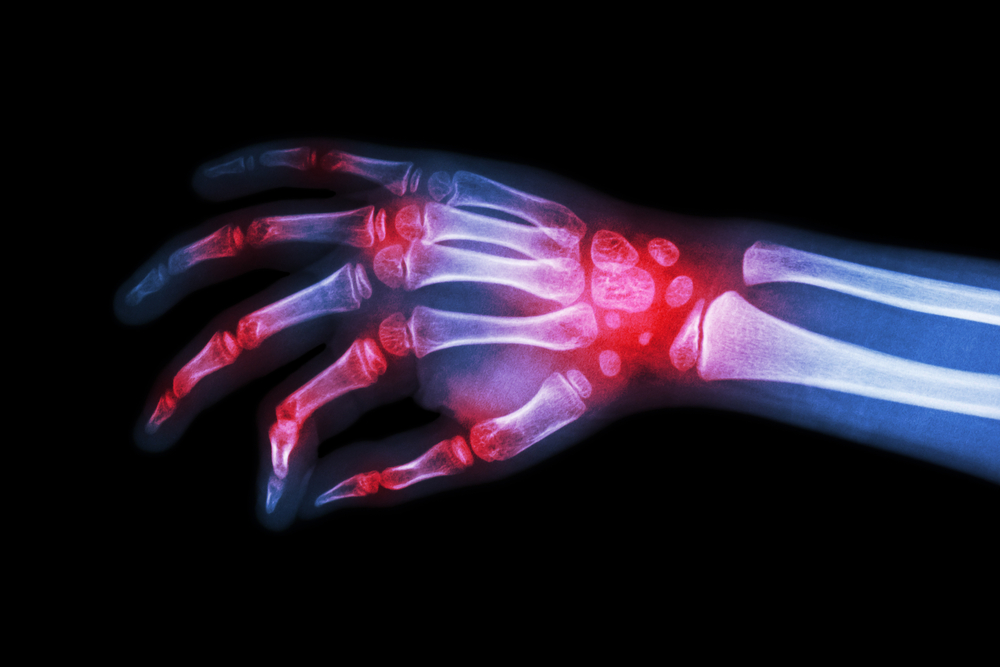

So what exactly is arthritis? The term arthritis refers to having problems with joints. Thus, arthritis is the swelling of one or more of your joints which lead to chronic pain, inflammation, loss of motion and stiffness. Flare-ups can also be very unpredictable. Therefore, first thing to know about arthritis is that it is painful. It affects millions of people in America and having a deeper understanding of it can assist reduce its impact. Below are the 10 things to know when dealing with arthritis.

The two main types of the condition are osteoarthritis and rheumatoid arthritis, but the symptoms are similar and can easily be confused. Osteoarthritis affects the joints and prevents them moving smoothly. Rheumatoid arthritis is a long-term, auto-immune condition that mainly affects the hands, feet and wrists, causing pain, swelling and stiffness in the joints. You may also experience problems elsewhere in your body, or even have other, vaguer symptoms like extreme tiredness or weight loss. You may even develop rheumatoid nodules, which are fleshy lumps that appear on your hands, feet or below the elbows.